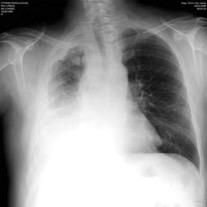

Chohan K et al. A review of respiratory manifestations and their management in Ehlers-Danlos syndromes and hypermobility spectrum disorders. Chronic Respiratory Disease. 2021 Hemotórax frecuente por rotura arterial. Enfermedad del tejido conectivo con hipermovilidad articular, textura de piel anormal y fragilidad del tejido conectivo. (Especialmente en el subtipo vascular)

Ehler Danlos vascular tipo IV. Hemoptisis con hemotórax y hematoma mediastínico. Embolización. 4º día: Fallece por rotura de la arteria esplénica.